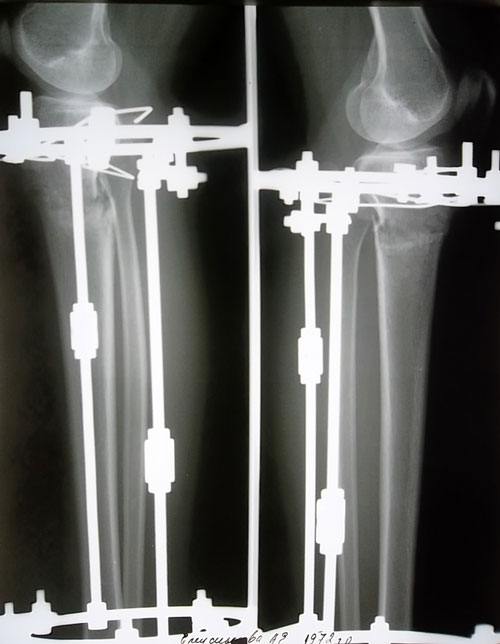

Рентгеновские снимки в 2 месяца после операции.

По рентгену у Вас всё отлично! В 3 месяца делайте ещё рентгеновский снимок и отправляйте нам, после этого планируйте снятие аппаратов.

Вложения

SAM_6664.JPG

SAM_6665.JPG